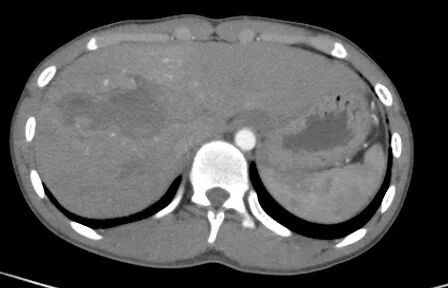

大肠癌

大肠癌是常见的恶性肿瘤,包括结肠癌和直肠癌。大肠癌的发病率从高到低依次为直肠、乙状结肠、盲肠、升结肠、降结肠及横结肠,近年有向近端(右半结肠)发展的趋势。其发病与生活方式、遗传、大肠腺瘤等关系密切。发病年龄趋老年化,男女之比为1.65:1。

升结肠癌并广泛转移

升结肠癌并肝转移